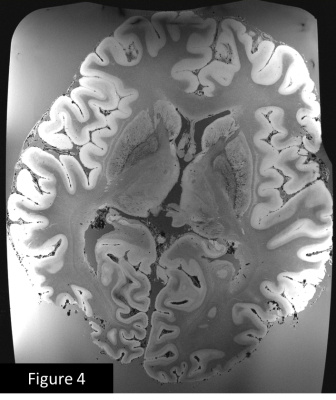

Previous work with ex vivo imaging has been done using a sophisticated process. The results shown here suggest that similar data(200um resolution) can be readily acquired without taking extraordinary or costly measures.

Figure 4. Ex vivo brain image at 200um resolution.